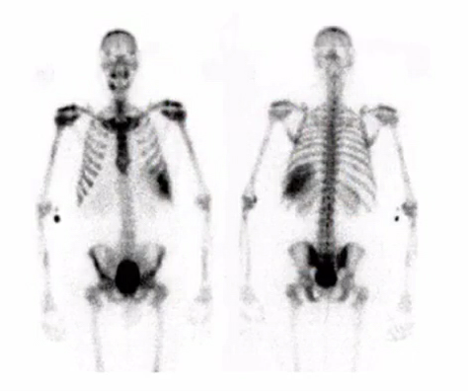

hot uptake in the metaphysis of a kid